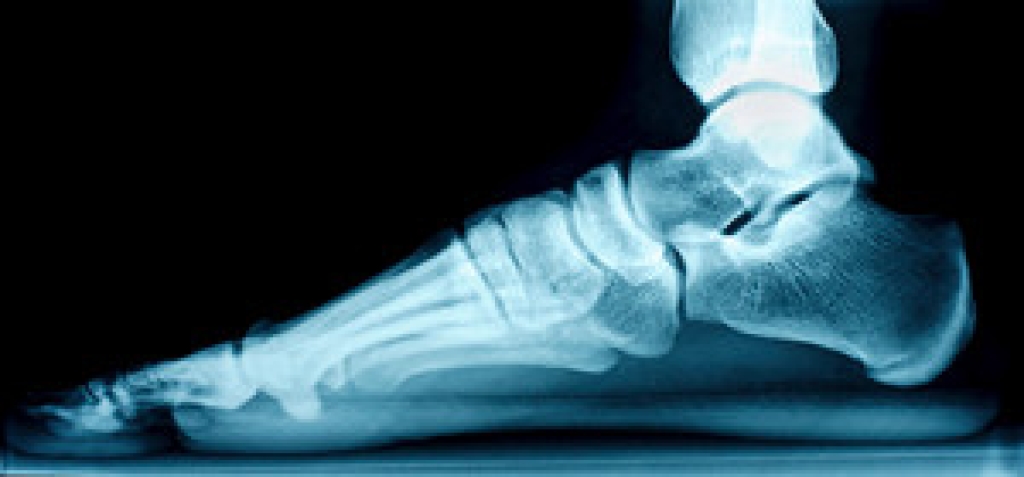

Orthotics – Custom made inserts can be used to help relieve pressure placed on the toes and therefore relieve some of the pain associated with it

Medications – Oral medications such as anti-inflammatories or NSAIDs could be used to treat the pain and inflammation hammertoes causes. Injections of corticosteroids are also sometimes used

Surgery – In more severe cases where the hammertoes have become more rigid, foot surgery is a potential option